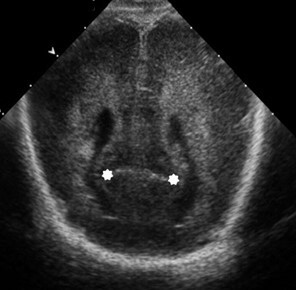

Neonatology Calcar Avis 3 Image